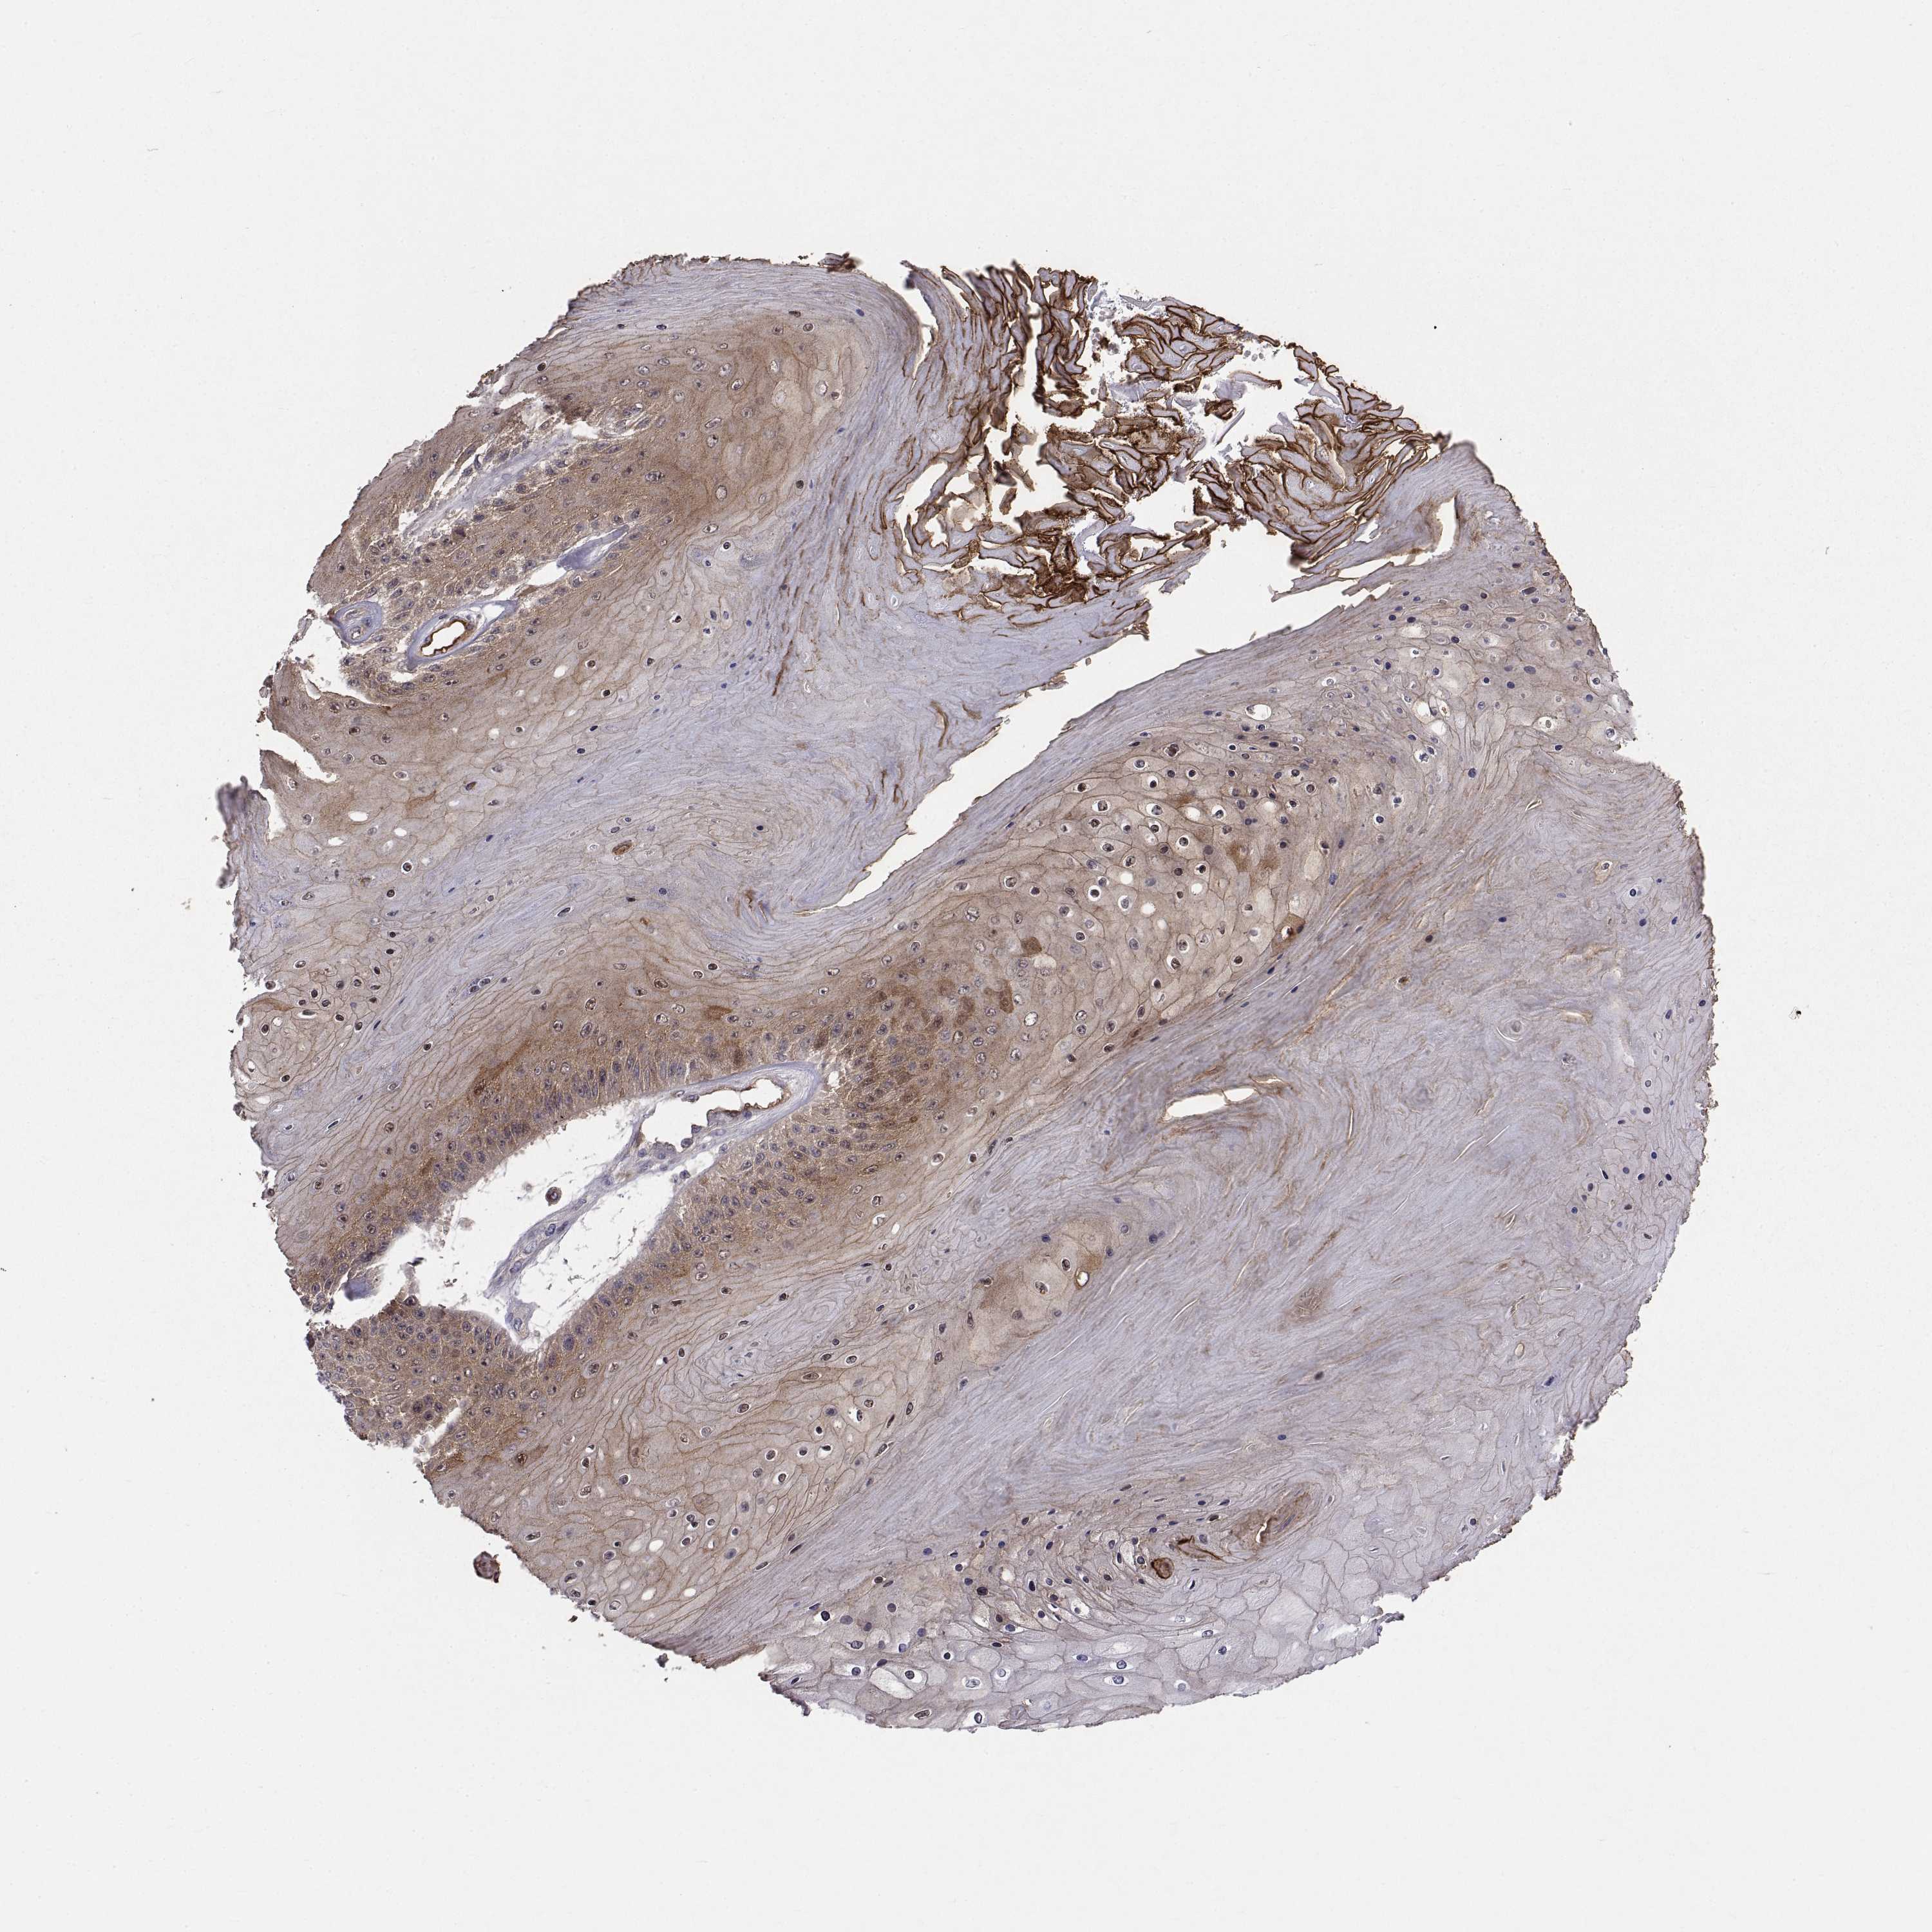

SKIN CANCER - Protein expressioni

A mouse-over function shows sample information and annotation data. Click on an image to view it in a full screen mode. Samples can be filtered based on level of antibody staining by selecting one or several of the following categories: high, medium, low and not detected. The assay and annotation is described here.

Each image is clickable and will lead to virtual microscopy that enables deeper exploration of all samples and also displays staining intensity scores, fraction scores and subcellular localization as well as patient and tissue information for each sample.

Antibody HPA027221

Basal cell carcinoma

Squamous cell carcinoma, NOS